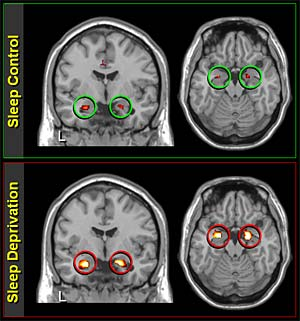

만성적인 수면 부족은 더 심각합니다. 6개월 이상 하루 6시간 미만 수면을 지속한 그룹에서는 해마(기억을 담당하는 뇌 부위)의 부피가 평균 8% 감소했다는 UCLA의 2024년 MRI 연구 결과도 있습니다.